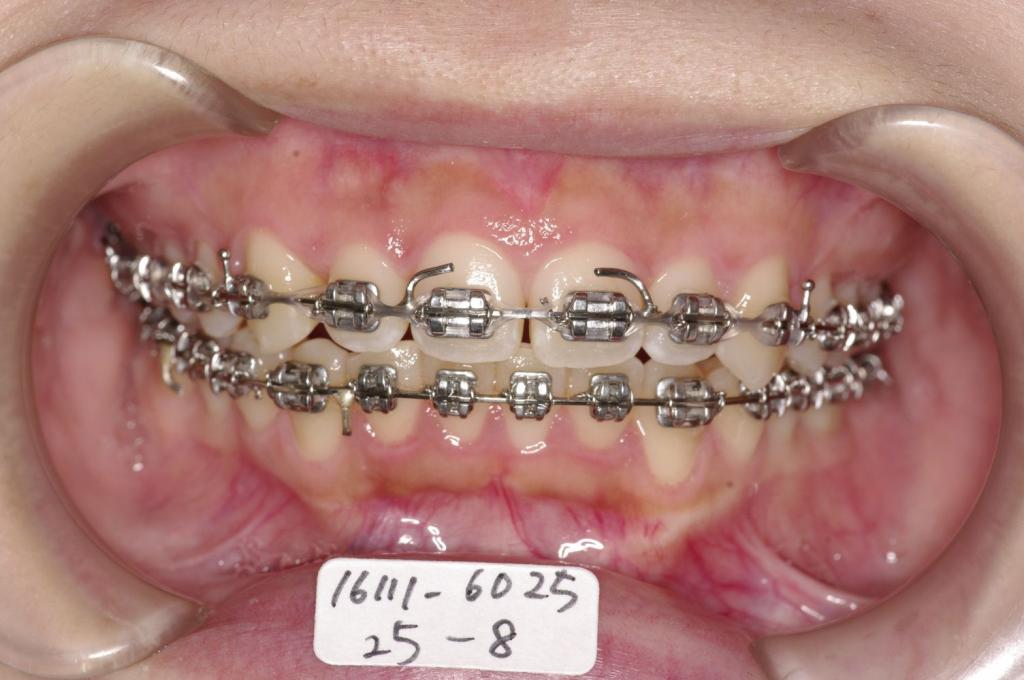

- 歯並び・咬み合わせ・八重歯・乱杭歯の矯正治療

- 咬み合わせが悪い